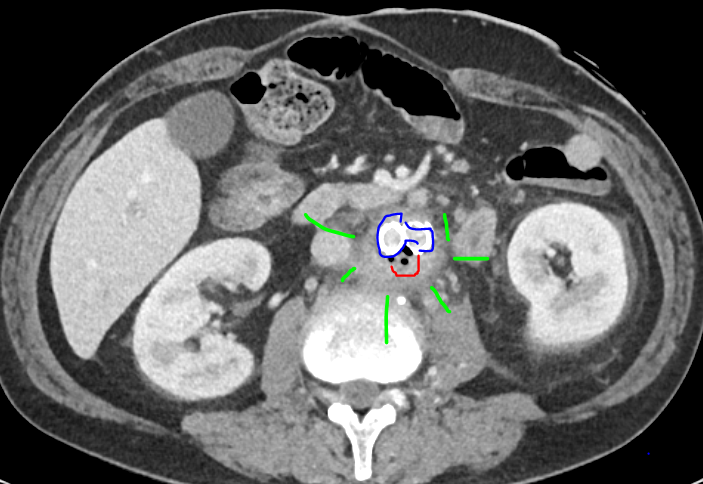

✨Up Next in our Member Spotlight Series - featuring Dr. Rocky Saenz! His passion for education has inspired numerous medical students and radiology residents. Dr. Saenz has made significant strides for DOs and radiologists, enhancing their recognition in the medical field.